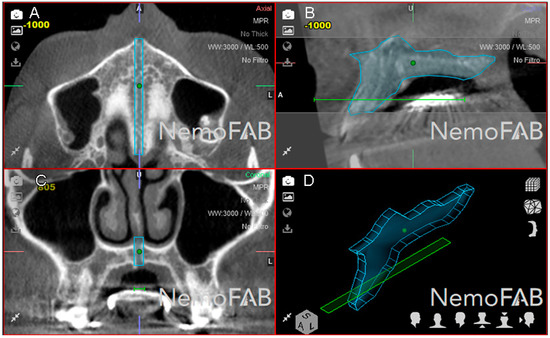

In addition, lineal measurements of the palatine suture expansion were also performed in order to analyze and compare the repeatability and reproducibility of the previously described conventional measurement technique [28,29] with the novel digital measurement method to quantify the volume of the midpalatal suture after rapid RME procedures. After uploading the images into three-dimensional orthodontic-planning software (NemoFAB 3D NemoStudio® 19.2.0 uv 89 2KT, Nemotec; Madrid, Spain) (Figure 5A), the midpalatal suture was aligned to the sagittal axis (Figure 5B) and the palatal plane was aligned to the axial axis (Figure 5C). Subsequently, horizontal lineal measurements from the cortex of the disjunction were performed at the central incisors, canines and first permanent molars (Figure 5D).

Figure 5.

(A) CBCT scan uploaded to the three-dimensional orthodontic-planning software, (B) alignment procedure of the CBCT scan, (C) alignment and (D) measurement procedure of the palatine suture expansion at the central incisors, canines and first permanent molars.